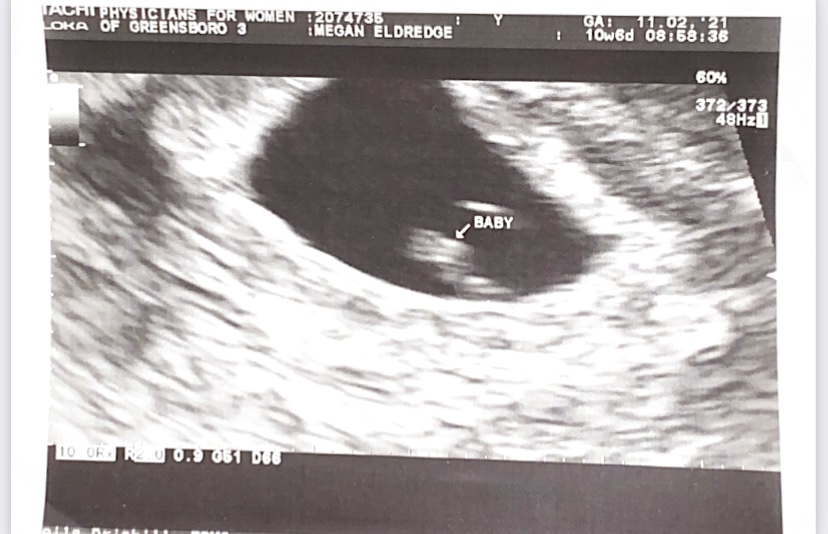

A positive pregnancy test two weeks before my 20th birthday. A pile of pregnancy tests with fading pink lines and nothing to show for it but a cancelled OBGYN appointment. An ultrasound of perfectly healthy baby at nine weeks with a late spring due date, hidden at the bottom of my sock drawer.

Having nothing to show for a pregnancy but a handful of tests is a horrible, empty feeling. I wanted so desperately to have an ultrasound, even if I couldn’t tell what I was looking at, just so I had proof that I was pregnant. Eventually, I convinced myself that without an ultrasound and since it was before 10 weeks, that it didn’t “count.” That I didn’t get to claim that I had a miscarriage. That I should just pretend it never happened. I threw away the pregnancy tests and deleted any pictures of them, and tried to move on.

In the long run, this delayed my healing process. I have since learned that even before ten weeks, it is absolutely a miscarriage/early pregnancy loss. The fact that there was no ultrasound or that I didn’t know the gender doesn’t mean that I had no reason to be sad.